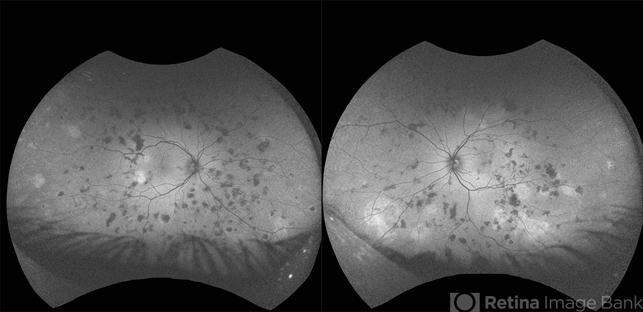

- Optos fundus autofluorescense image shows multiple hyper and hypo autofluorescent lesions corresponding to active and healed lesions in the midperipheral retina and periphery suggestive of varied stage presentation of lesions.